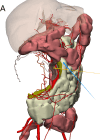

This case report presents the surgical management of a complex abdominal sarcoma in a 33-year-old female patient, emphasizing the pivotal role of advanced imaging and three-dimensional (3D) printing technology in optimizing surgical outcomes. The study aimed to explore the clinical value of integrating computed tomography, magnetic resonance imaging, and patient-specific 3D-printed models for preoperative planning, intraoperative navigation, and postoperative evaluation. A multidisciplinary team utilized Mimics23 software to generate a detailed 3D reconstruction of the tumor and its intricate anatomical relationships with the ileocecal region, appendix, and colon. This model guided the precise resection of a 15 × 10 × 10 cm high-grade sarcoma, minimizing damage to adjacent critical structures. The technology-enhanced approach resulted in complete tumor excision with clear margins, and postoperative no complications. This case underscores the potential of 3D visualization and printing to address the challenges of complex abdominal sarcomas, offering a paradigm for personalized surgical strategies in oncology.